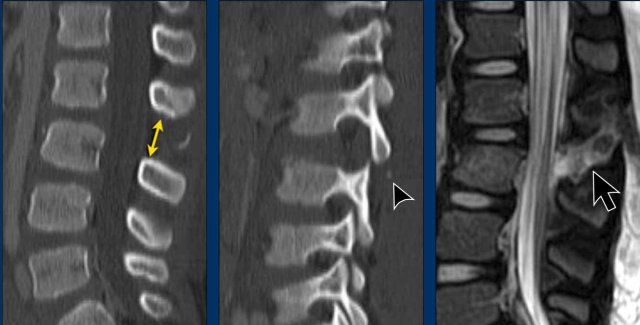

These images are of a young child with a spinal injury.

Findings

1. Clear widening of the interspinous distance (yellow arrow)

2. Black arrowhead: small avulsion fracture to the flexion distraction

3. MRI better depicts the ligamentous injury, which was suspected on CT

Conclusion

Injury type B2